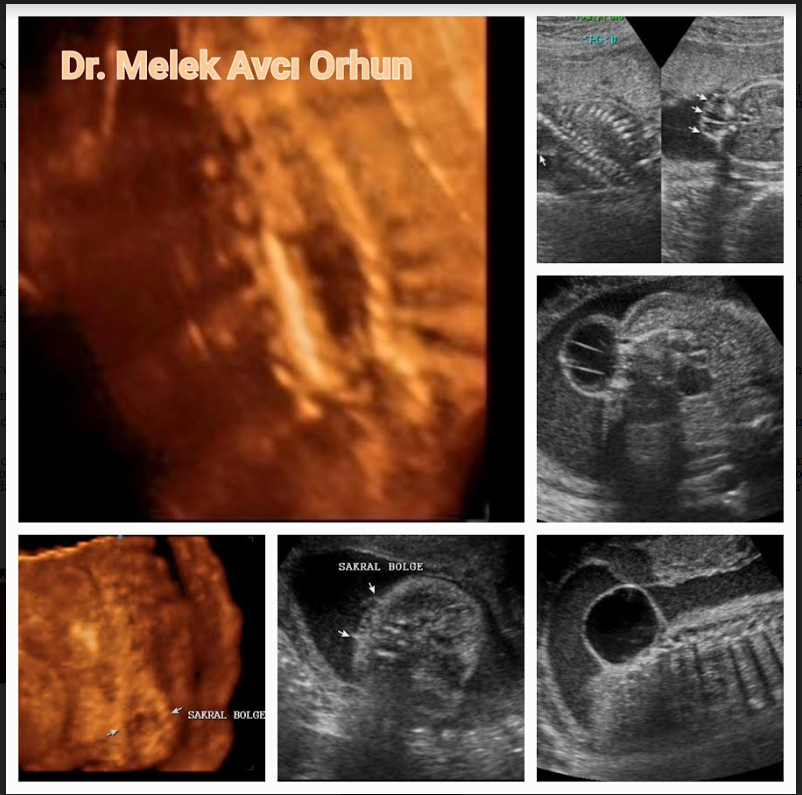

Nöral Tüp Defektleri ve Prenatal Tanısı

AKRANİ-ANENSEFALİ KOMPLEKSİ, Kafa tabanı ve yüz kemik yapılarının gelişip kafatası kemik yapılarının gelişmediği, beyin dokusunun b...